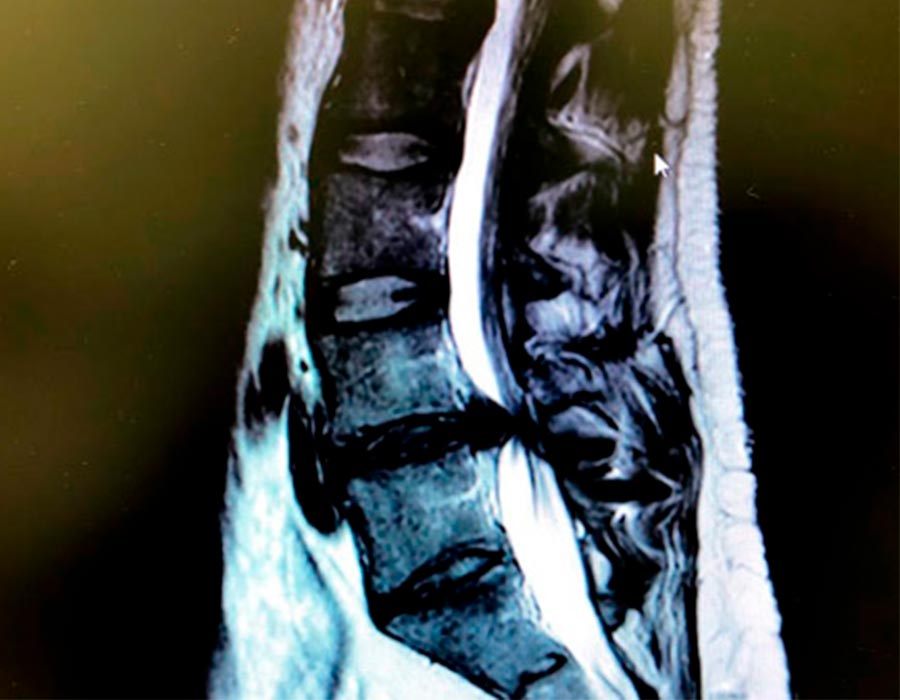

Preoperatorio

Esta artrodesis le ha provocado una nueva hernia discal lumbar en el nivel que hay por encima debido a la movilidad propia de este segmento. Esta nueva hernia le provoca una compresión en el canal medular y en los nervios que contiene.

Hernia discal lumbar a extraer